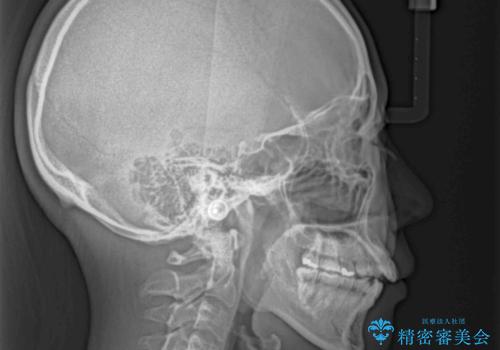

残存乳歯とオープンバイト インビザラインによる矯正治療

- 前歯のデコボコと咬み合わせを気にして来院された患者様です。

左上奥歯には乳歯が残存しており、後続永久歯は舌側に転位していました。

また、舌の突出癖の影響で上下前歯が接触していないオープンバイトとなっており、奥歯に負担のかかる咬み合わせとなっていました。

乳歯を抜歯し、舌側の永久歯を引っ張り出すこととしましたが、希望のインビザラインでは移動量が大きすぎて対応できない可能性があったため、ワイヤー装置にて改善することとしました。

ワイヤー装置にてある程度歯列が改善されたところで、上下をインビザラインにて矯正治療を行うこととしました。

舌のトレーニングをしっかりと行ってくださり、前歯部のオープンバイトは大幅に改善されました。

もう少しでよりタイトに前歯が接触できそうでしたが、患者様がもう十分とのことで治療を終了しました。